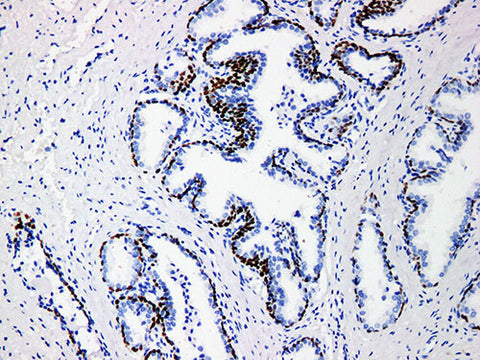

| Applications | IHC-P |

| Cellular Localization | nucleus |

| Tissue Specificity | Prostate cancer |

P63 gene is one member of the p53 gene family, which positions on chromosome 3q27-28, and encodes more than 6 major isomers that respectively treat transcriptional kinase activity, death induction activity (TAP63) and chromic inactivation activity. In embryo period, many kinds of epithelium and organs need P63 protein. P63 protein is expressed in myoepithelial cells and the effect is better than SMA, but is not expressed in myofibroblasts. Recent research shows that p63 is a marker of prostate basal cells, it is not expressed in the majority of prostate tumors, and its significance is similar to 34bE12. Since p63 is nuclear positive staining and P504S is cytoplasmic staining, the combination of them makes it easier to determine the results.